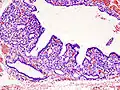

Hyperthyroidism is one of the most common endocrine conditions affecting older domesticated housecats. In the United States, up to 10% of cats over ten years old have hyperthyroidism.[64] The disease has become significantly more common since the first reports of feline hyperthyroidism in the 1970s. The most common cause of hyperthyroidism in cats is the presence of benign tumors called adenomas. 98% of cases are caused by the presence of an adenoma,[65] but the reason these cats develop such tumors continues to be studied.